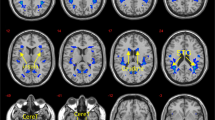

Cortical grey matter morphometry results indicated that increased scores on intelligence tests related primarily to increased thickness and volume of parietal regions (Fig. 3). Increased WASI full scale scores associated with increased volume in the left superior parietal lobule (SPL) (Fig. 3a; p < 0.005). Likewise, analysis of subtest scores (Fig. 3b) revealed increased performance on the similarities subtest also related to increased thickness (p = 0.001) and volume (p = 0.006) in the left SPL, as well as increased thickness in the right inferior parietal lobule (IPL) (p < 0.01) and increased volume in the right visual cortex (p < 0.02). Additionally, increased vocabulary subtest scores associated with increased volume in the right fusiform gyrus (p < 0.03).

a Increased intelligence (WASI full scale) related to increased volume in the left superior parietal lobule (SPL). b Increased performance on the similarities test were associated with increased thickness and volume in the left SPL, as well as increased thickness in the right inferior parietal lobule (IPL) and increased volume in the right visual cortex, whereas increased vocabulary scores were associated with increased area in the right fusiform gyrus. c Dual regression results indicated that increased WASI performance showed increased representation of a visual ICN, which specifically related to increased connectivity with the right dorsolateral PFC, lingual gyrus, cuneus, and precuneus

To assess functional attributes related to performance on the WASI, we examined resting-state functional connectivity using ICA. Results indicated that higher intelligence scores significantly related to increased connectivity of a visual ICN with the dorsolateral PFC, lingual gyrus, cuneus, and precuneus (Fig. 3c; p < 0.03). This same finding for the precuneus also was found for the similarities subtest (p < 0.03). Performance on the WASI full scale and subtest scores did not show significant associations with subcortical structure or white matter integrity.

D-KEFS color-word interference test

D-KEFS Color-Word Interference Test (CWIT) performance was significantly related to cortical thickness in frontal and parietal regions (Fig. 4a), such that increased inhibitory control ability associated with increased thickness in the left SPL (p < 0.007) and left lateral orbitofrontal cortex (OFC) (p < 0.03). Subcortical morphometry results indicated that increased performance on the D-KEFS CWIT related to a significant change in shape and increased volume of the left nucleus accumbens (Fig. 4b; t = 2.94, p = 0.004), suggesting that increased inhibitory control was associated with increased size of the left nucleus accumbens. D-KEFS CWIT performance did not show any significant associations with FA measures of white matter structural integrity.

a Increased inhibitory control, as measured by the D-KEFS CWIT, associated with increased thickness in the left superior parietal lobule (SPL) and the left-lateral orbitofrontal cortex (OFC). b Increased CWIT scores also related to significant shape changes and increased volume for the left nucleus accumbens. c Dual regression results indicating increased D-KEFS CWIT scores related to increased connectivity of the default mode network with bilateral insular and central-opercular regions, as well as the right amygdala and hippocampus

Resting-state ICA analyses further revealed that increased performance on the D-KEFS CWIT associated with increased functional connectivity of the default mode network (DMN) with bilateral insular and opercular regions, as well as the right amygdala and hippocampus (Fig. 4c; p < 0.03). This suggested that increased inhibition related to increased across-network connectivity of the DMN.